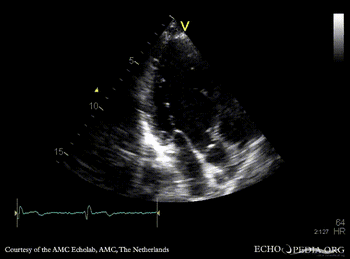

E00729.gif E00730.gif

A3CH: subvalvular membrane A3CH with Color Doppler: high velocity flow in LVOT